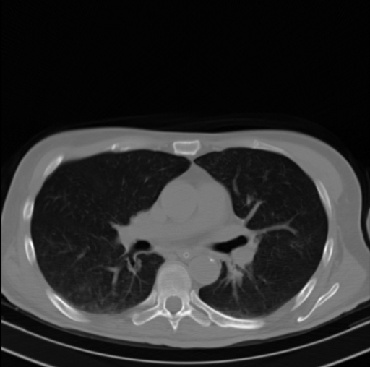

Early and reliable COVID-19 diagnosis based on chest 3-D CT scans can assist medical specialists in vital circumstances. Deep learning methodologies constitute a main approach for chest CT scan analysis and disease prediction. However, large annotated databases are necessary for developing deep learning models that are able to provide COVID-19 diagnosis across various medical environments in different countries. Due to privacy issues, publicly available COVID-19 CT datasets are highly difficult to obtain, which hinders the research and development of AI-enabled diagnosis methods of COVID-19 based on CT scans. In this paper we present the COV19-CT-DB database which is annotated for COVID-19, consisting of about 5,000 3-D CT scans, We have split the database in training, validation and test datasets. The former two datasets can be used for training and validation of machine learning models, while the latter will be used for evaluation of the developed models. We also present a deep learning approach, based on a CNN-RNN network and report its performance on the COVID19-CT-DB database.